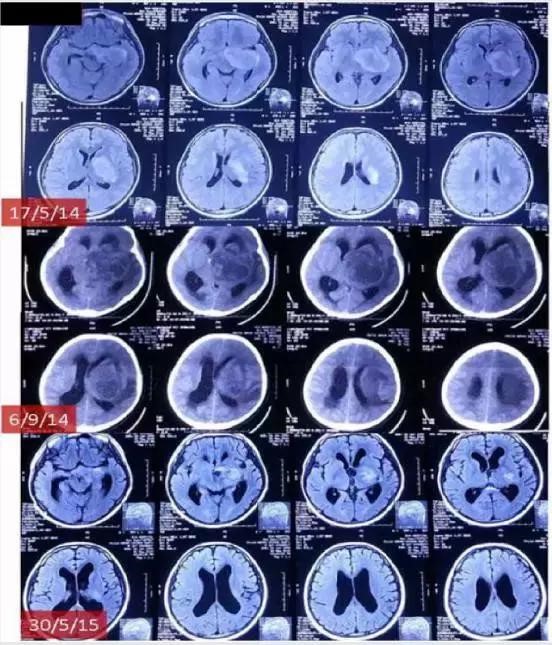

图1 电场疗法治疗脑肿瘤的大致过程:计算电场,治疗前后行CT检查。

治疗案例一、患者男性,16岁,诊断左基底神经节脑肿瘤(星形细胞瘤):肿瘤位于左基底神经节,中线右移,压迫中脑(MRI 2014年5月17日),导致严重头痛及右侧肌肉运动、视力及听力受损。患者初始一般状况非常差,瘫痪。电场治疗4月后,MRI示肿瘤恶化(2014年9月6日),同时患者一般状况恶化。进而将治疗服装进行改动使其更集中在深部肿瘤上。使用新设计的电场服装治疗3月后,患者临床症状包括运动、视力及听力明显改善。使用新服装6月后,MRI(2015年5月30日)示肿瘤明显缩小,脑积水减少,中线移位消失。